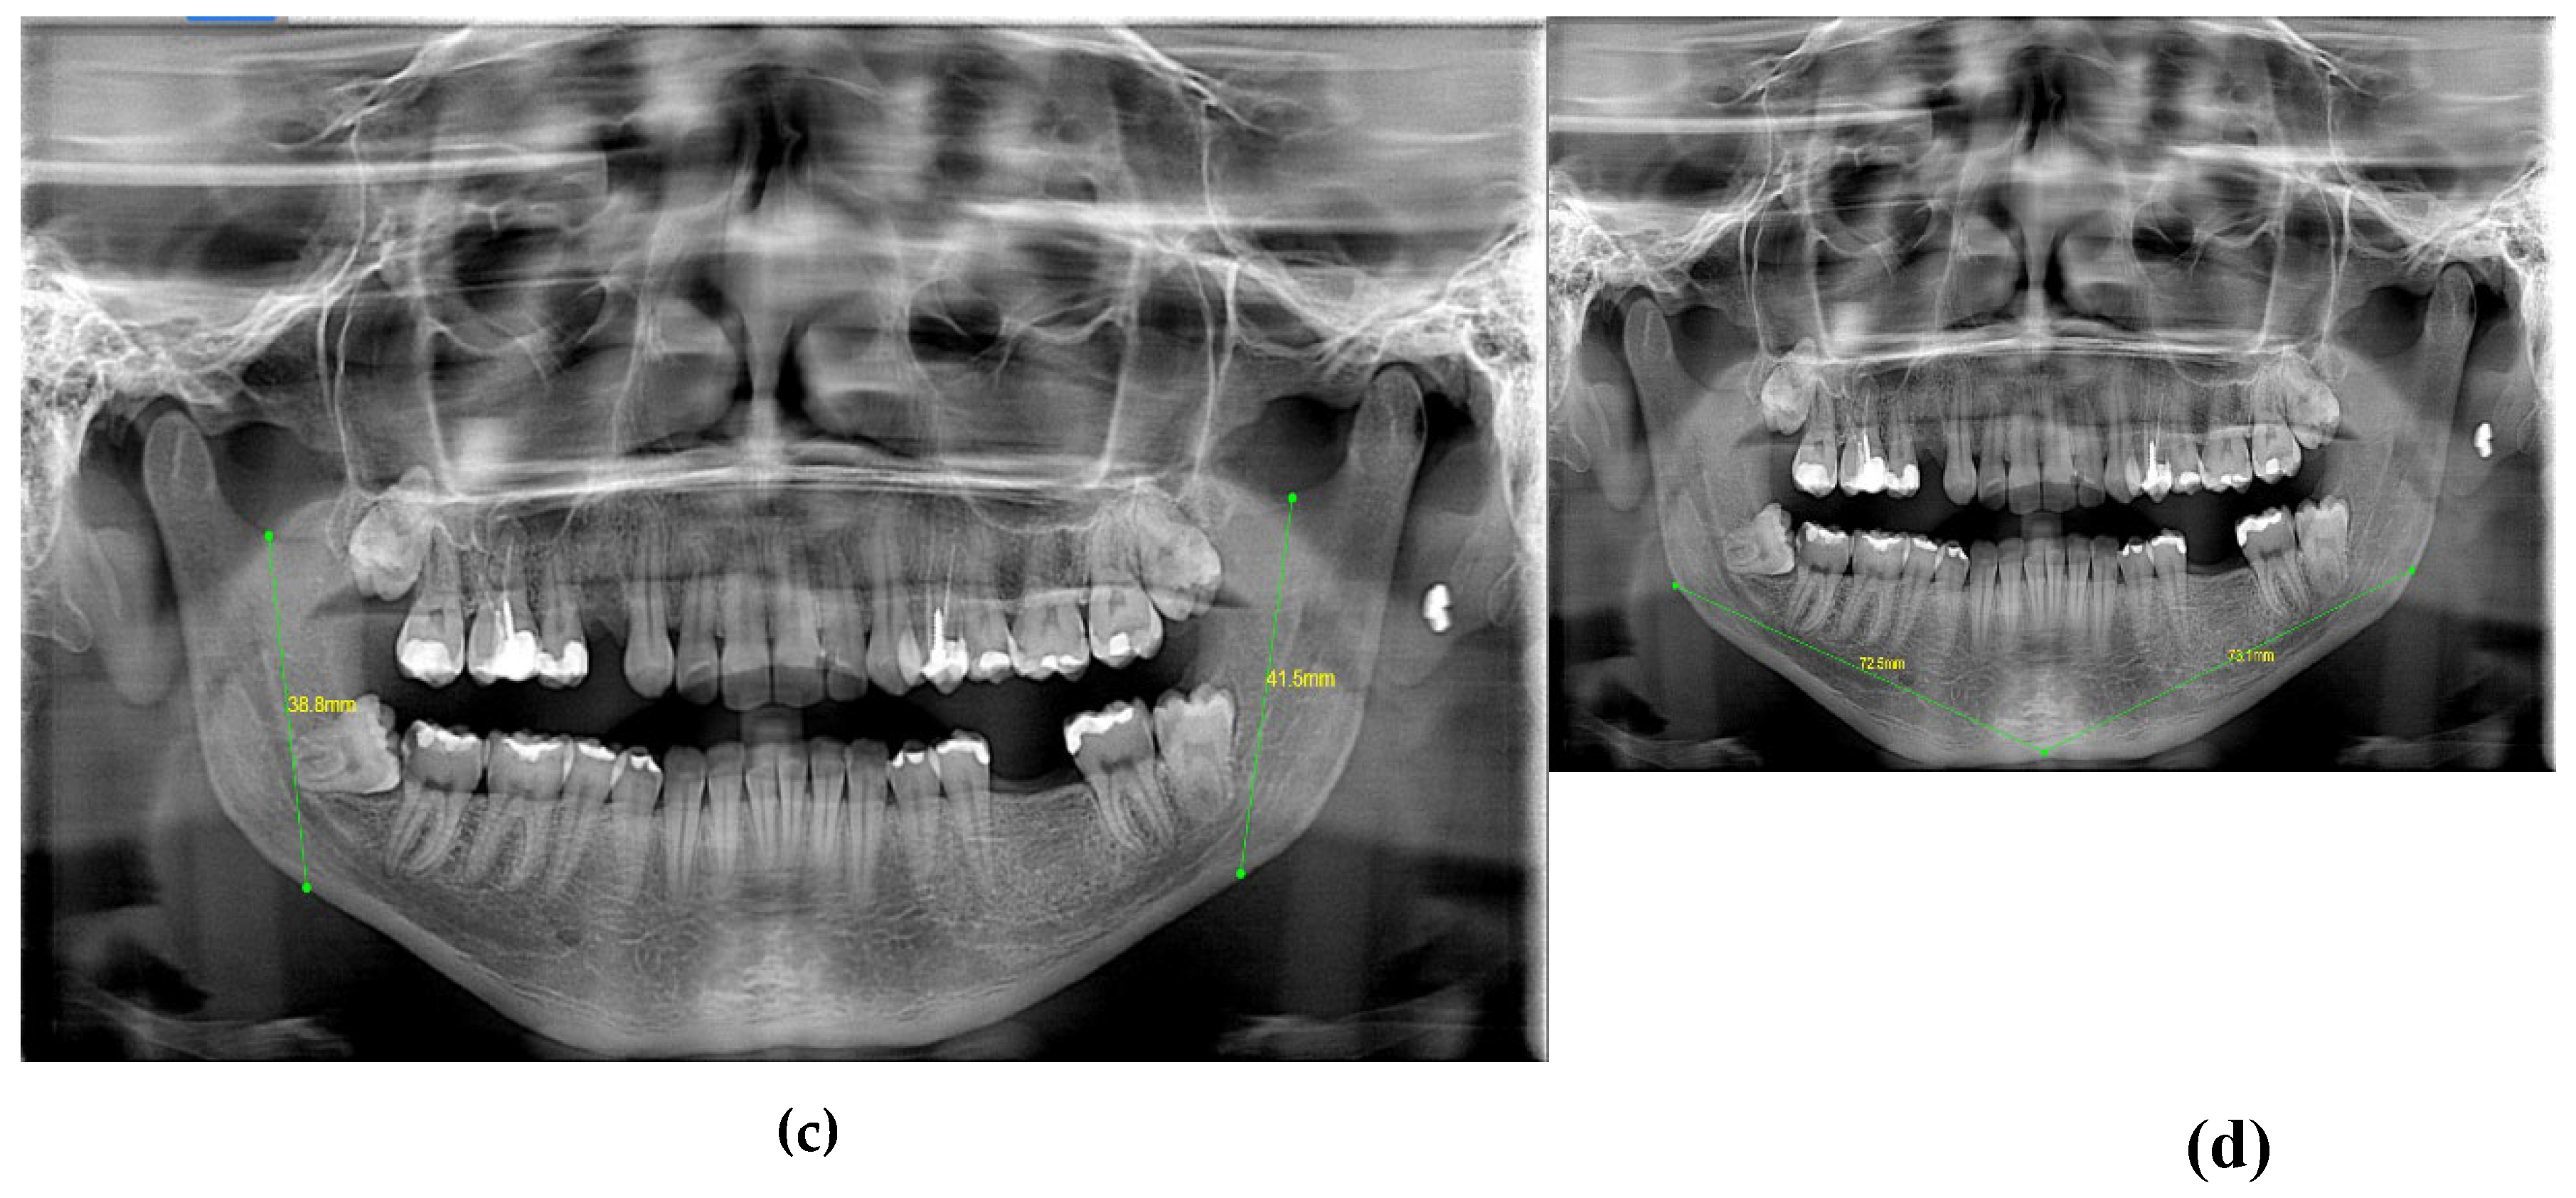

| 3 | GONIAL ANGLE (°) | At lateral cephalograms, it was determined at the junction of the mandibular and ramus planes. A line tangent to the lower border of the mandible and another line tangent to the distal border of the ascending ramus and the condyle on either side were drawn in order to measure the gonial angle in the panoramic radiographs [20]. The mandibular plane and the ramus plane’s built point of junction. |

| 4 | RAMUS HEIGHT | (mm) The distance between Ag and Snp [21]. |

| 5 | MANDIBULAR BODY LENGTH | (mm) The distance between point Go and point M [21]. |